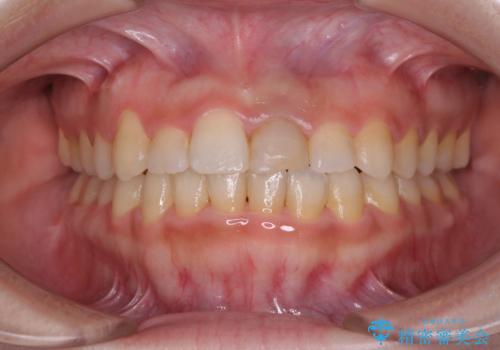

- 前歯のクロスバイトと神経を取り除いた後に変色してしまった前歯を気にして来院された患者様です。

ワイヤー矯正により矯正治療を行った後に、前歯の補綴治療を行うこととしました。

インビザラインでの矯正治療も十分に対応可能でしたが、自己管理の煩わしさから、ワイヤー矯正を行うこととしました。